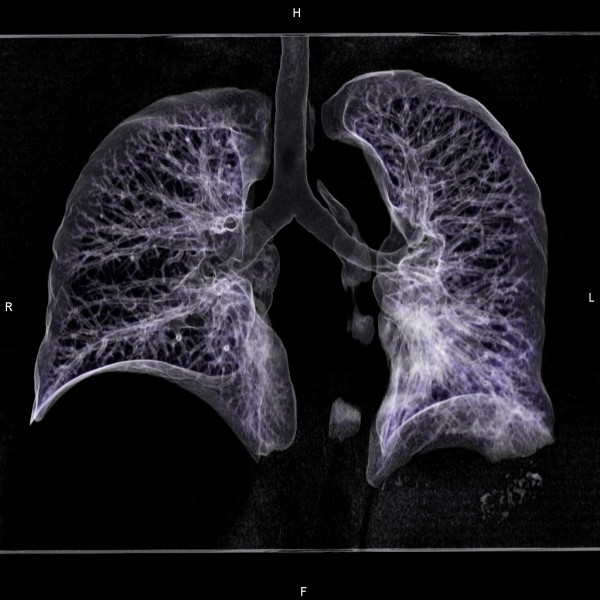

根據《TVBS新聞網》報導,這名病患在母親因肺癌離世後,心生警惕前往醫院檢查,結果真的發現罹患肺癌,但所幸是初期,立即進行手術處理。不料,他想起弟弟最近有持續咳嗽的症狀,便建議他也去檢查,沒想到X光檢查出現異常,進一步安排電腦斷層檢查後,竟然已經是第四期肺癌,甚至已經出現轉移的情況。